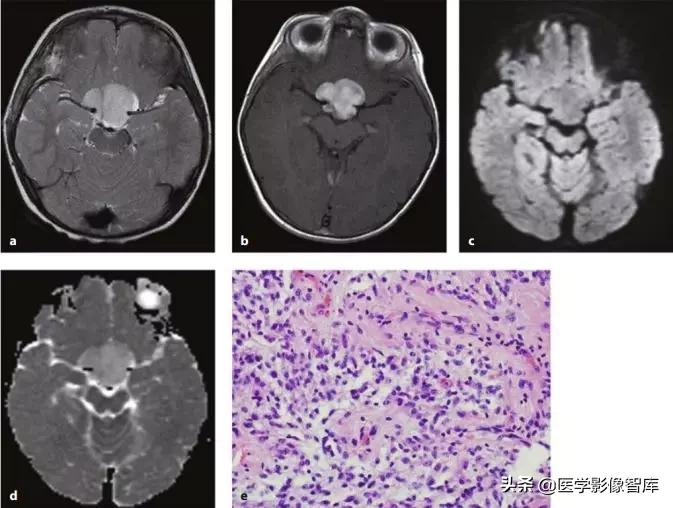

图5 环形强化对比(脑脓肿 vs 胶质母细胞瘤)

脑脓肿主要是血源性感染,额、顶叶最常见,后颅窝小于15%,多位于灰白质交界处。一般为单发,多发少见(免疫抑制状态多见)。脓液表现为长T1长T2,FLAIR低信号,DWI高信号,ADC低信号;脓壁则包含了纤维成分,T1呈等/稍高信号,T2等/稍低信号,均匀环形强化(较光滑,深部薄,浅部厚);可以有子灶(卫星灶),破裂后形成小脓肿。

图6 脑脓肿(弥散受限)